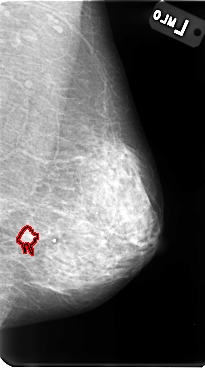

B_3085_1.LEFT_MLO

LEFT_MLO LINES 4800 PIXELS_PER_LINE 2656 BITS_PER_PIXEL 12 RESOLUTION 50 OVERLAY

FILE: B_3085_1.LEFT_MLO.OVERLAY

TOTAL_ABNORMALITIES 1

ABNORMALITY 1

LESION_TYPE MASS SHAPE IRREGULAR-ARCHITECTURAL_DISTORTION MARGINS SPICULATED

ASSESSMENT 4

SUBTLETY 4

PATHOLOGY MALIGNANT

TOTAL_OUTLINES 1

BOUNDARY